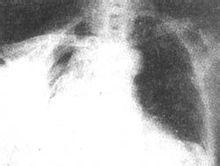

结核性脓胸多由于肺结核空洞或胸膜下干酪样病灶破裂,感染胸膜而引起,间或可由脊椎结核的椎旁脓肿直接蔓延所致。肺结核外科手术并发支气管胸膜瘘或胸膜腔感染也可引起脓气胸。此外,渗出性胸膜炎积液长期不吸收,有一部分可逐渐发展成脓胸。自从抗结核药物广泛应用以来,结核性脓胸的发病率已大为减低。